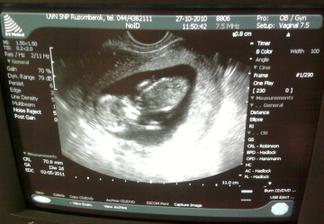

27.10.2010 druhá poradňa za nami, malinké sa vrtilo, mávalo ručičkami, veľmi ma to dojalo :°) 13+4tt meriame 70,8mm, pridaná ďalšia foto :°)